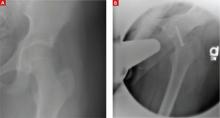

FIGURE 2

One hip fixed, trouble in the other

Seven months after surgery on her right hip, the patient sought treatment for her left hip (A) and underwent a second pinning procedure (B).